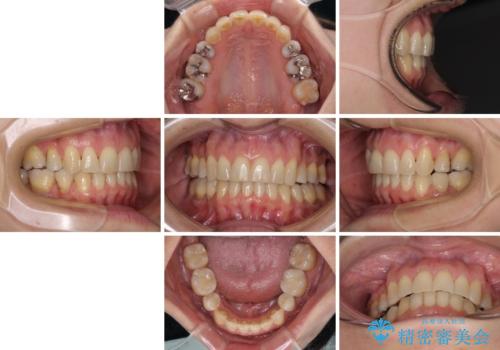

インビザライン・ライトは、製作できるアライナーの枚数に制限があるため、移動可能な量に限りがあります。

軽微な後戻りの治療であったため、十分に治療を行うことができました。

口を開けたときに金属が見えなくなり、患者様には大変満足していただきました。